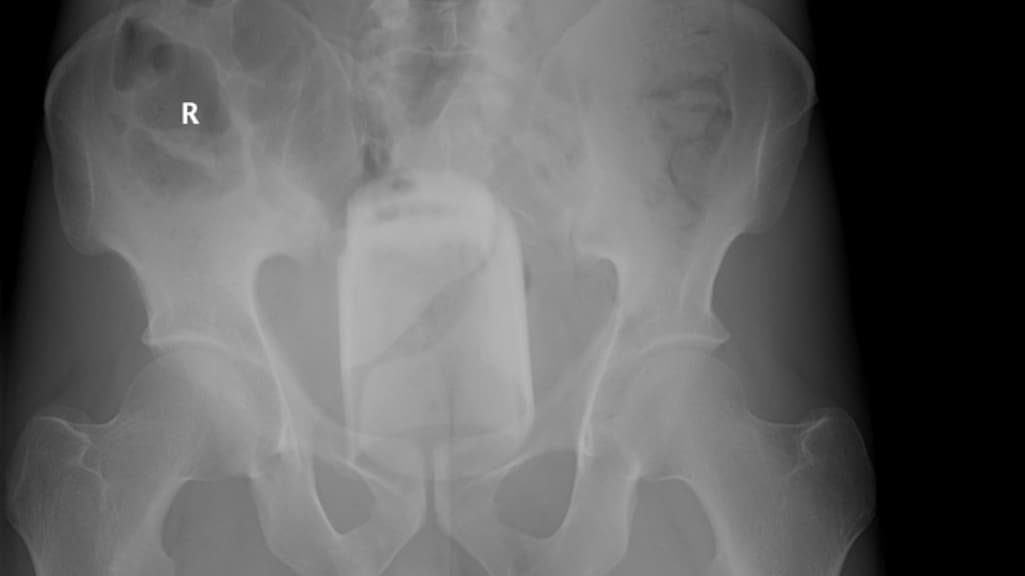

"Bierflesjes, wortels, tandenborstels, vazen en stenen, als het past, gaat het erin", zegt ze. Daar kunnen normen of richtlijnen weinig aan voorkomen. Wat wel zou helpen, is minder schaamte. De röntgenfoto's zijn afkomstig van een website voor en door artsen, waar zij foto's delen als naslagwerk.